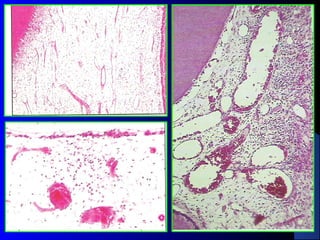

Acute Reversible Pulpitis

Histopathological Features:

Pulp hyperemia (dilatation of blood vessels).

Exudation.

Inflammatory cell infiltration (neutrophils).

Reactions usually remain localized adjacent to

the cause.

Acute Irreversible Pulpitis

 Histopathological

Features:

Inflammation involves the whole dental pulp.

Vascular dilatation and edema.

Inflammatory [granular cell] infiltration.

Odontoblasts near to the cause are destroyed.

Formation of a minute pulp abscess.

In a few days pulp undergoes liquefaction

and necrosis.